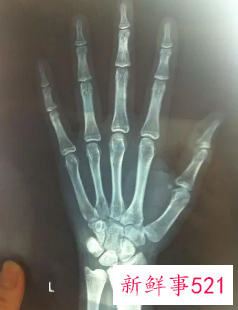

比较简单的方法就是去拍一个X光,借助于骨骼在X光摄像中的特定图像来确定。通常要拍摄人左手手腕部的X光片,医生通过X光片观察左手掌指骨、腕骨及桡尺骨下端的骨化中心的发育程度,来解读确定骨龄。

一般手腕部最理想,因为腕关节和手骨骼数目多,骨骺数目多,集中了大量的长骨、短骨和圆骨,且出现和闭合时间跨度大,是观察骨龄的理想部位能够集中地反映了全身骨骼生长和成熟状况。

骨龄鉴定是指人的生长发育可用两个“年龄”来表示,即生活年龄(日历年龄)和生物年龄(骨龄)。骨龄是骨骼年龄的简称,借助于骨骼在X光摄像中的特定图像来确定。在了解人的骨龄情况时,通常要拍摄人左手手腕部的X光片,医生通过X光片观察左手掌指骨、腕骨及桡尺骨下端的骨化中心的发育程度,来确定骨龄。